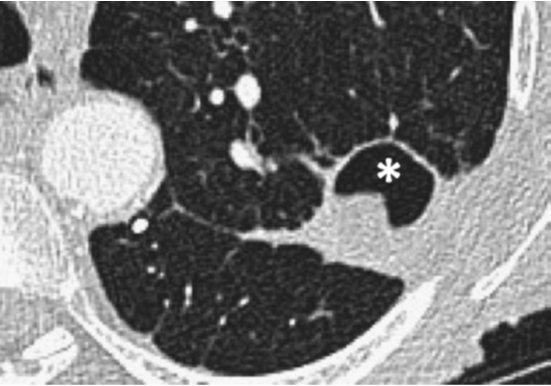

友情提示:不要忘记肺梗死也会形成空洞。典型的梗死区基底部较宽位于胸膜,尖端圆隆指向肺门,呈楔形,在慢性和急性肺栓塞中均可形成空洞(发生率分别为11%和5%)(图 7)。约50%合并空洞的肺梗死会引发二重感染,其中梭状芽胞杆菌更易在梗死区引起坏死性空洞性肺炎。除肺栓塞外,瘤栓、血管内异物、肺动脉肉瘤和大血管的血管炎也会引起空洞性肺梗死。

图 7 慢性肺栓塞患者,右肺上叶见楔形宽基底实变区伴空洞(*)。